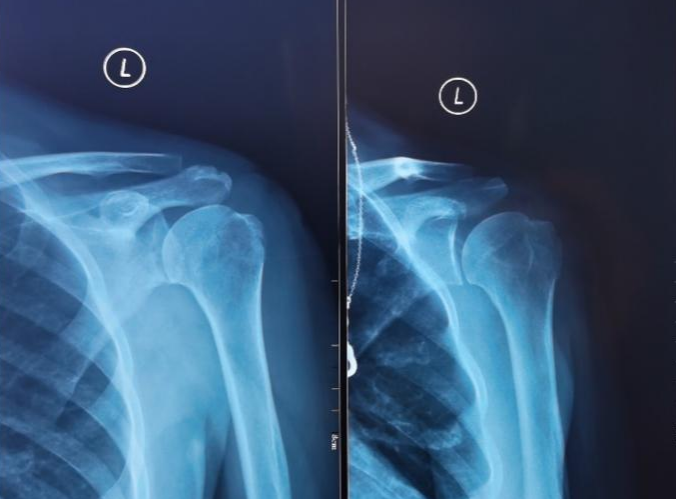

患者术前X线检查可见肩关节脱位及肱骨大结节骨折

术后复查可见肩关节及大结节骨折位置恢复良好